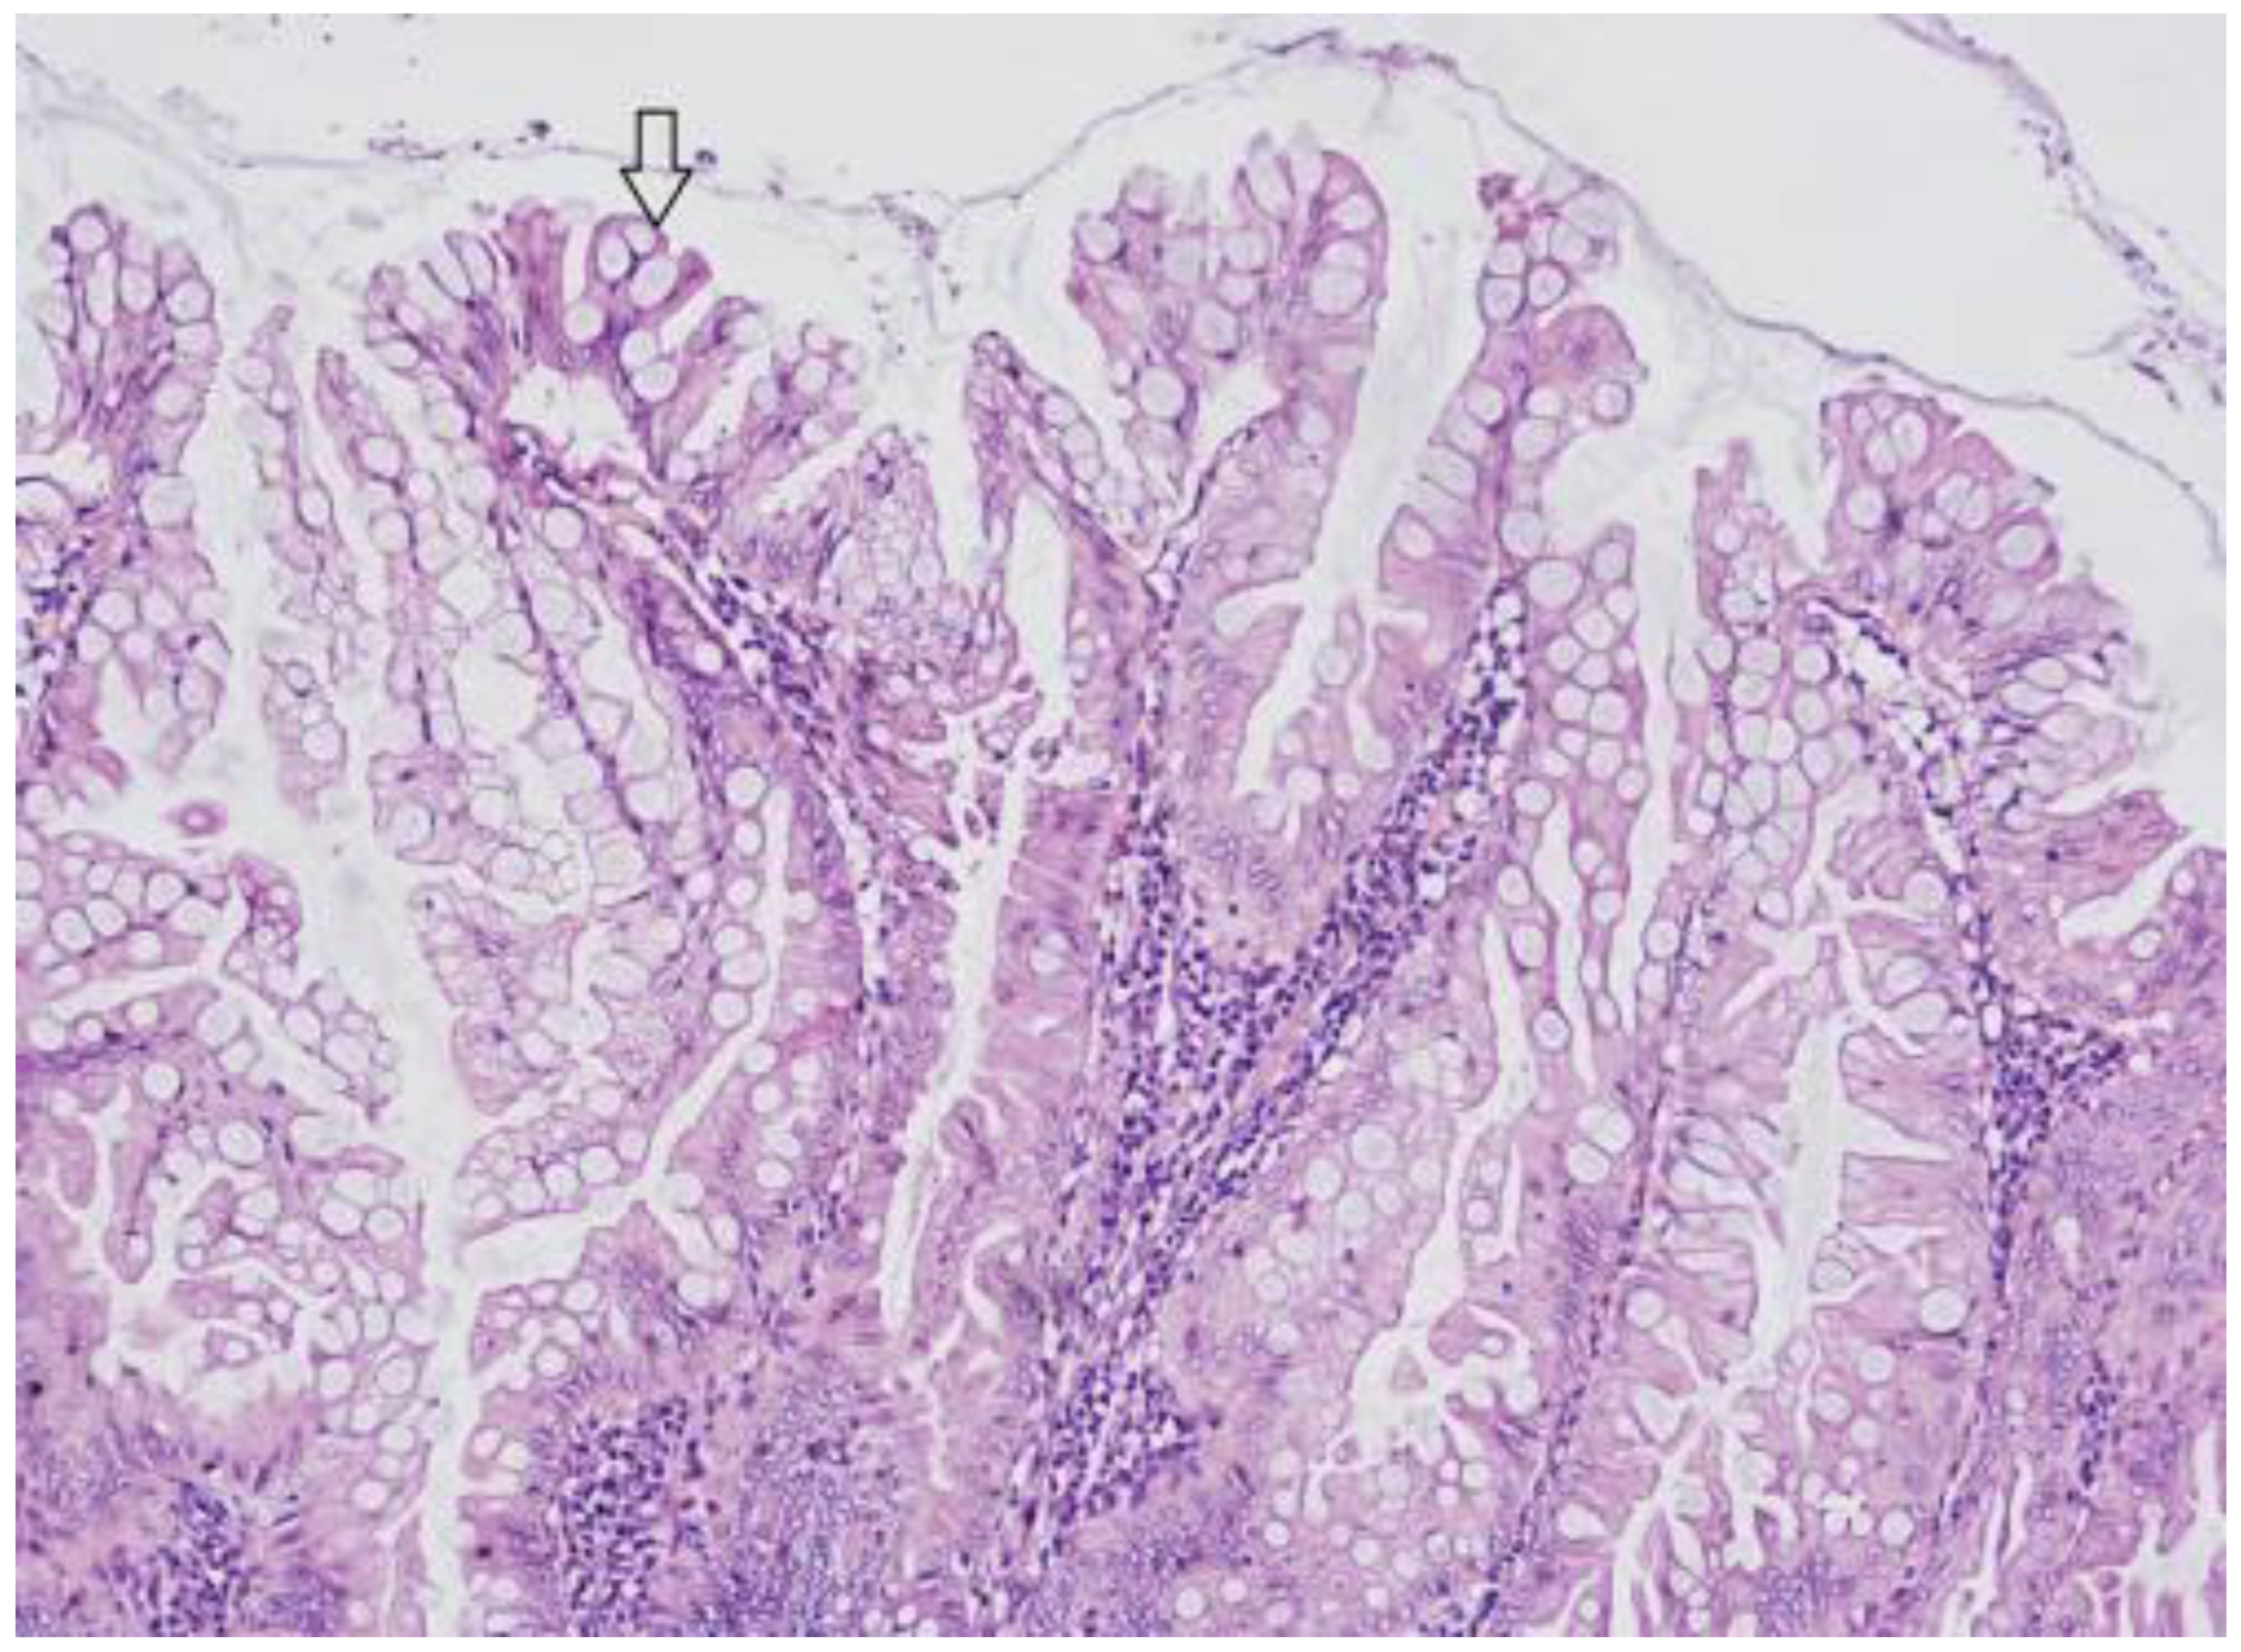

3.3. Traditional Serrated Adenoma (TSA)